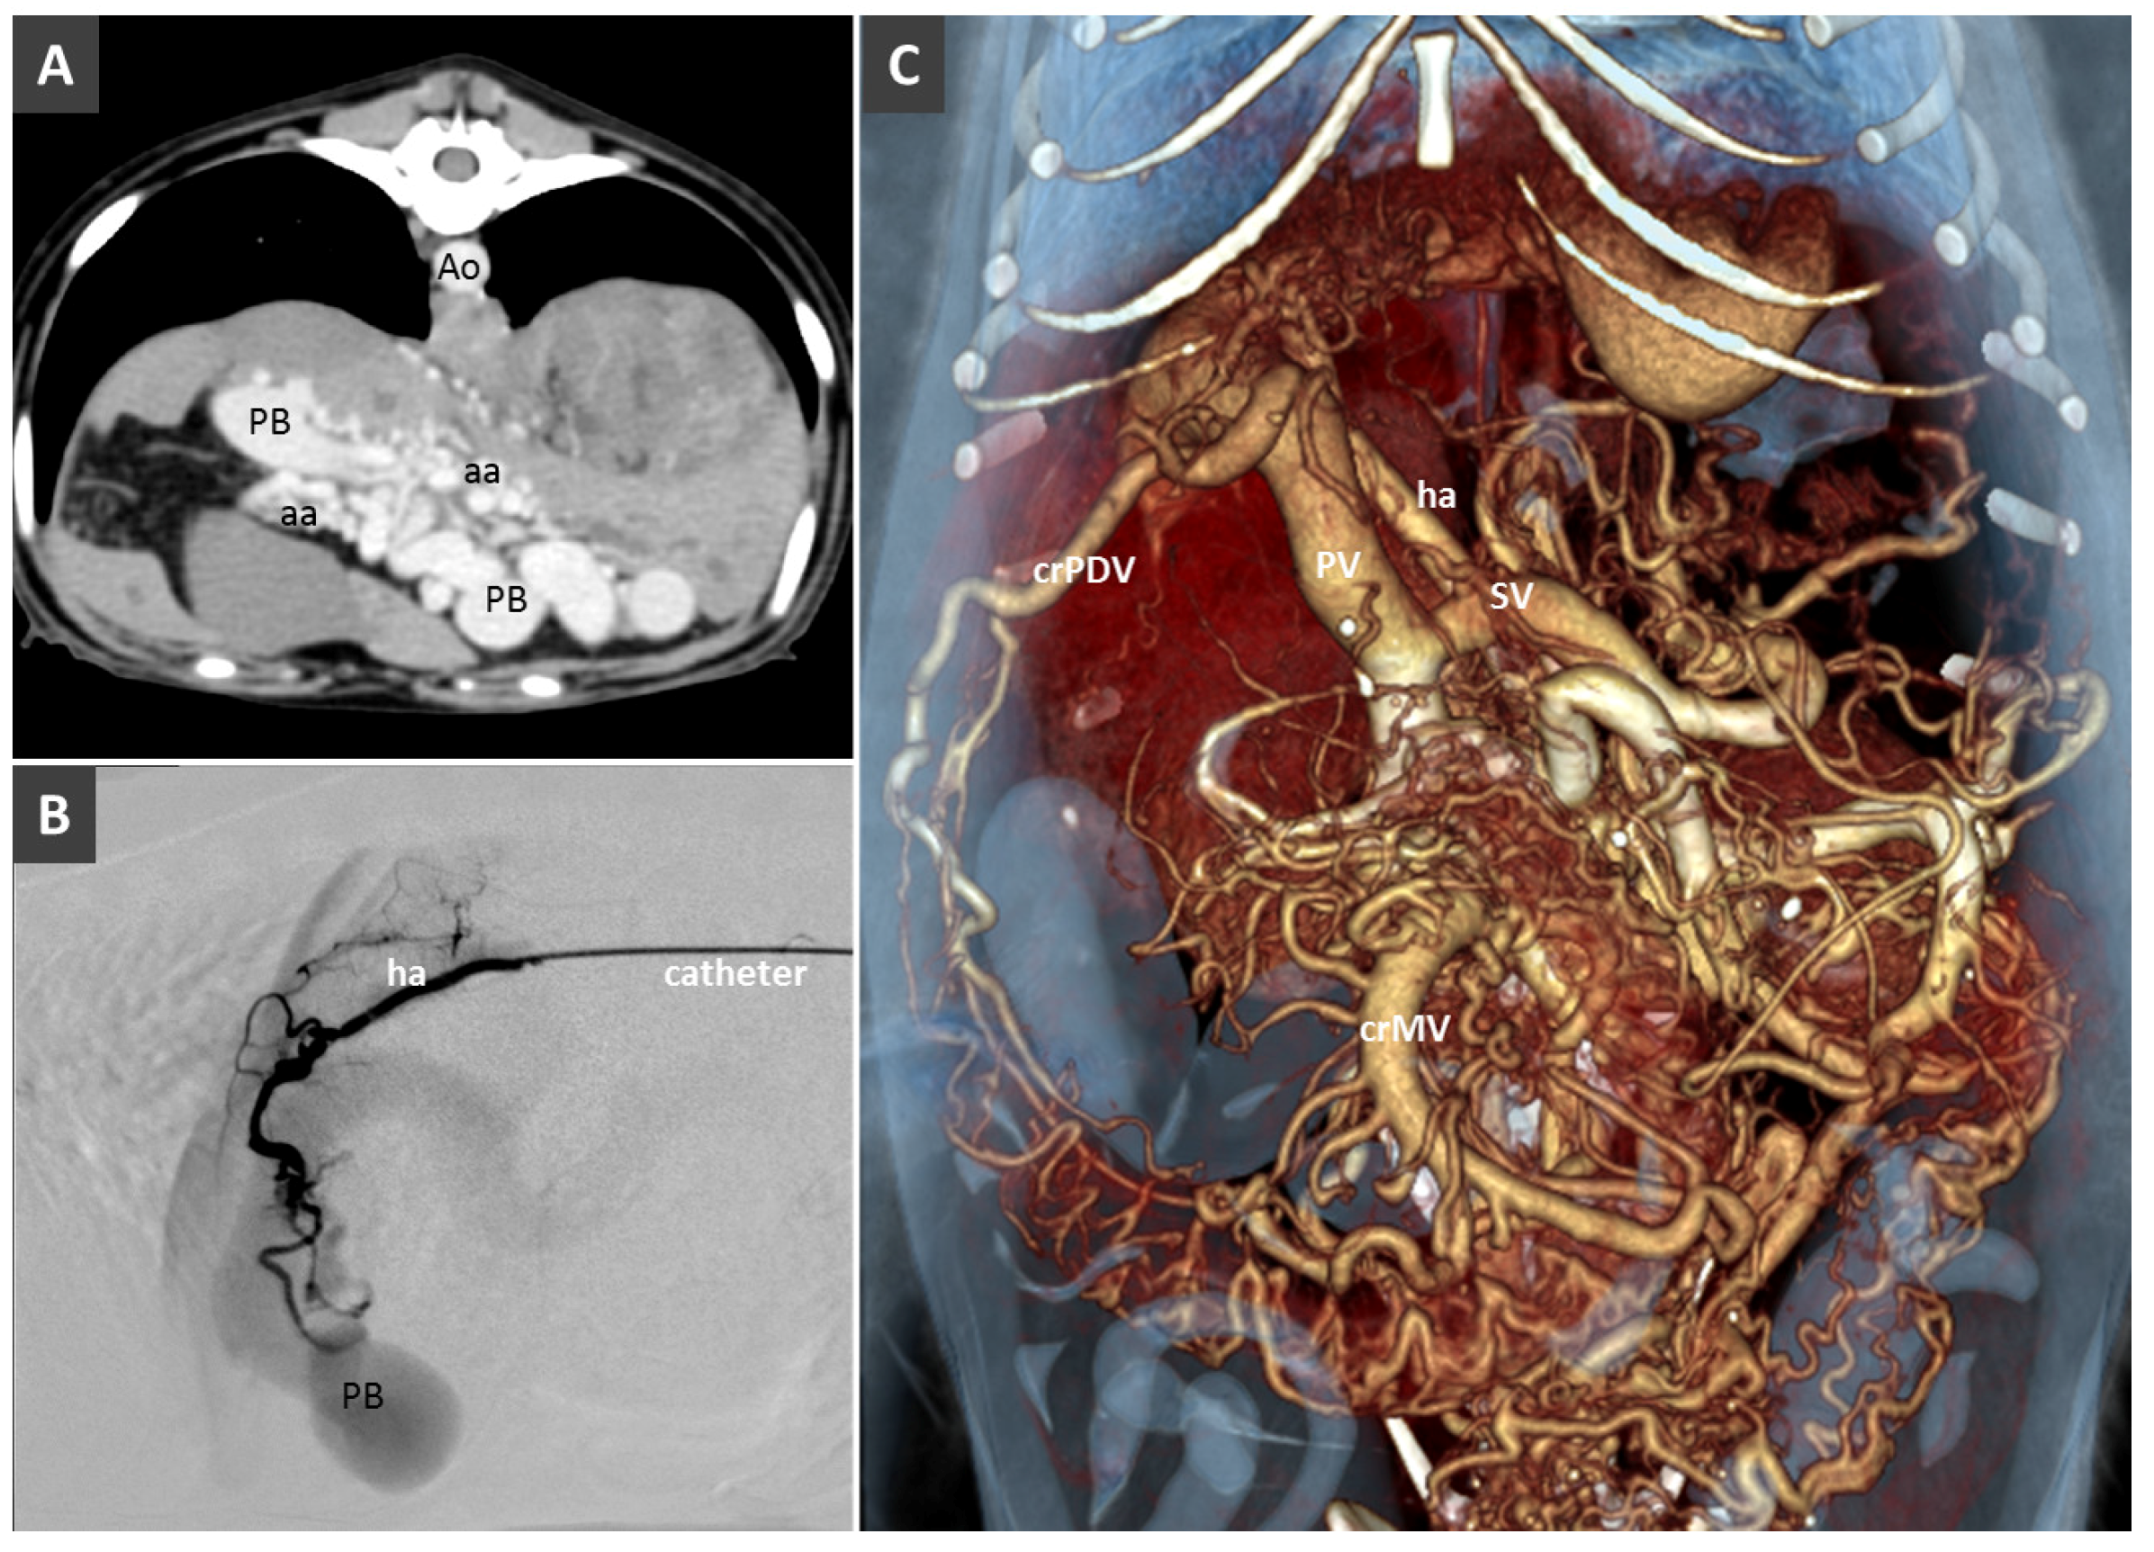

High-Flow Anomalous Portal Connections

Congenital Portosystemic Shunt